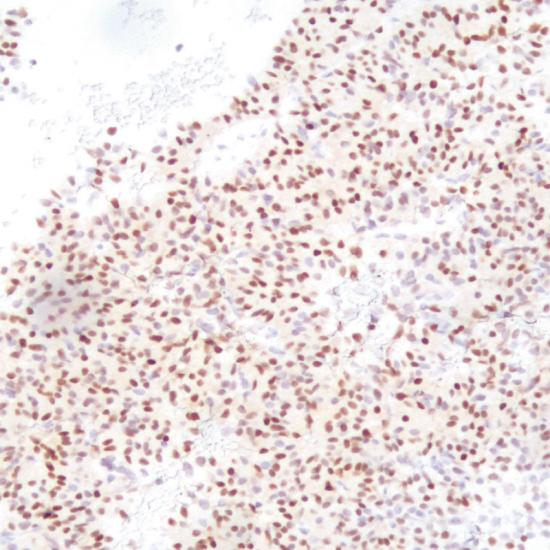

T-PIT(TBX19)

細胞核

垂體腺瘤

T-PIT(TBX19)是阿片-促黑素細胞皮質(zhì)激素(POMC)譜系與促腎上腺皮質(zhì)激素細胞轉(zhuǎn)錄因子。形態(tài)學(xué)特征和免疫學(xué)標記,用于腺瘤分類的轉(zhuǎn)錄因子可分為三組:嗜酸性譜系,對PIT-1陽性,會導(dǎo)致生長激索瘤,泌乳索細胞和促甲狀腺激索腫瘤;類固醇生長因子-1 (SF-1)陽性的腺瘤,導(dǎo)致促性腺瘤;腺瘤呈T-PIT陽性,導(dǎo)致促腎上腺皮質(zhì)激索腺瘤。